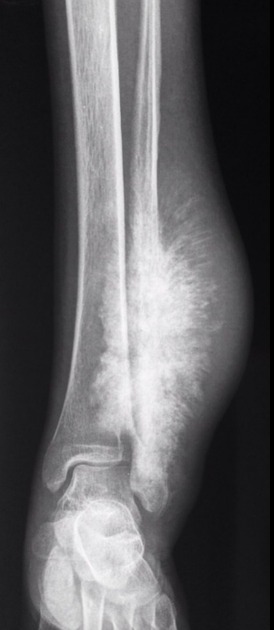

Giant cell tumour And Osteosarcoma

Giant cell tumour And Osteosarcoma from image.slidesharecdn.com

Osteosarcoma is a type of bone cancer that usually develops in the osteoblast cells that form bone. It happens most often in children, adolescents, and young adults. Imaging characteristics of primary osteosarcoma: J med assoc thai¼chotmaihet thangphaet 2010; Osteosarcoma is a bone tumor and can occur in any bone, usually in the extremities of long bones near metaphyseal growth plates. Average age at diagnosis is 15. Specifically, it is an aggressive malignant neoplasm that arises from primitive transformed cells of mesenchymal origin (and thus a sarcoma). Imaging characteristics of primary osteosarcoma: Osteosarcoma of the femur with skip, lymph node, and lung metastases.

Osteosarcoma can cause knee pain or pain and swelling in the affected area. Effects of glucosamine, chondroitin, or placebo in patients with osteoarthritis of hip or knee: Imaging characteristics of primary osteosarcoma: Osteosarcoma is a very rare type of cancerous bone tumor that usually develops in teenagers. Primary osteosarcomas typically occur at the metadiaphysis of long bones in the appendicular skeleton, most commonly at the following sites Average age at diagnosis is 15. Children treated with radiation for another cancer also. Osteosarcoma is the most common type bone cancer seen in children to young adults. Osteosarcoma is the most common type of bone cancer, and accounts for about 3% of boys are more likely to have osteosarcoma than girls, and most cases of osteosarcoma involve the knee. Osteosarcoma is a type of bone cancer that usually develops in the osteoblast cells that form bone. Adjuvant multiple drug chemotherapy for osteosarcoma of. Found as incidental finding or presents with a fracture. * oarsi recommendations for the management of hip and knee osteoarthritis, part ii: An algorithm recommendation for the management of knee osteoarthritis in europe and internationally. Osteosarcoma of the femur with skip, lymph node, and lung metastases.